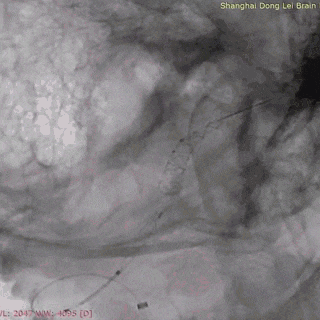

强易达(Choydar)血流导向密网支架头端封闭结构,减少对血管壁的损伤,安全性好。

独特热处理技术增强了贴壁性。整体释放操作简单,无需过多推挤,显影清晰。

强易达(Choydar)血流导向密网支架2-3mm直径可通过其0.017微导管输送系统释放,通过性好,在此病例中也减少了更换微导管带来的操作和风险。

强易达(Choydar)血流导向密网支架打开贴壁良好,2mm和3mm支架在不同血管直径中均展现了良好的贴壁,小血管中表现优异。2mm-6.5mm直径可选,型号多,应用范围广。